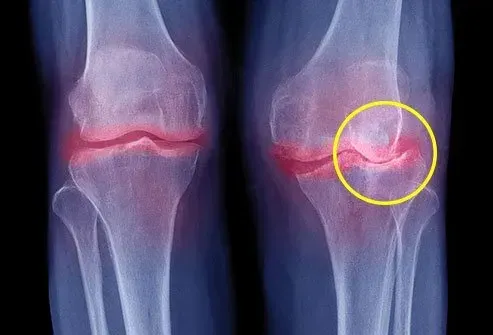

Votre cartilage caoutchouteux empêche vos os de se frotter les articulations. Le cartilage permet à vos articulations de glisser en douceur et il amortit les os dans des circonstances normales. Mais l'arthrose (OA) provoque la rupture du cartilage. Cela laisse vos articulations douloureuses avec un gonflement et un mouvement restreint.

L'OA peut provoquer la rupture de vos articulations et de votre cartilage avec le temps. Cela conduit à des croissances osseuses appelées éperons osseux. Votre corps essaie de réagir pour protéger vos os en devenant enflammé. Mais certains des produits chimiques impliqués dans le processus inflammatoire peuvent endommager encore plus le cartilage.

L'OA est le problème conjoint chronique le plus courant. Près de 30 millions d'Américains ont l'arthrose. Bien que toute articulation puisse être blessée par l'OA, elle a tendance à avoir un impact sur certaines zones plus que d'autres. Les doigts sont vulnérables à l'arthrose, tout comme les genoux des hanches et le bas du dos. Toute personne de tout âge peut être affectée par l'arthrose, mais elle est plus courante pour les personnes de plus de 65 ans. En fait, une personne sur 12 a plus de 60 ans.